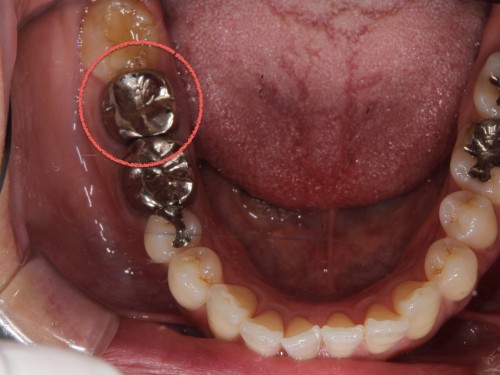

この方の初めて来院された時のお写真です。

今まで歯科に行ってはどうにもならないと言われてきた患者さんです。

歯磨き指導などは今まで受けたことがなくこのまま悪くなるのを待つだけと言われていたそうです。

レントゲン写真ですが歯周病の重度の進行があります。